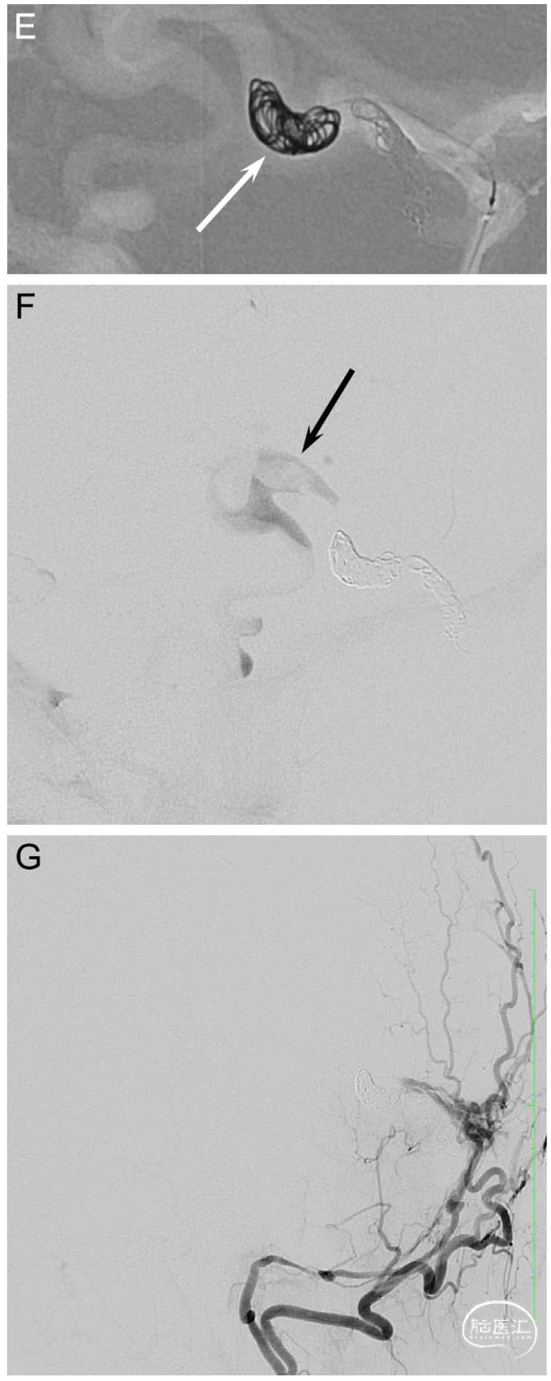

Fig. 1. A 52-year-old woman (patient no. 3) with headache and pulsatile tinnitus underwent an MRI showing dilated veins in the posterior fossa. A diagnostic DSA confirmed a high-grade tentorial DAVF near the confluence (Borden type III, Cognard type IV). A.-B. Left CCA and left selective posterior meningeal artery (PMA) injections in lateral views show a DAVF (arrow) with deep venous drainage and several venous ectasias. C. Lateral view showing the transfistulous approach performed via the left PMA using a triaxial system with a 5F Sofia and a 1.3F Headway™ Duo (Terumo Neuro) reaching the proximal venous outflow (arrow). D.-E. Roadmap in lateral views. The fistulous outflow consisted of two adjacent, first separately draining and then merging veins, both of which were tightly packed with coils (arrows). Due to the high flow, the 2nd and more enlarged distal portion (E) required an oversized HydroCoil18 (10 mm x 31 cm, Terumo Neuro) for a stable basket to be filled with smaller Target XL coils (Stryker). F. Late-phase left ICA control run in lateral view shows formation of thrombus in the dilated draining vein as a filling defect (arrow). G. Left occipital artery control run in lateral view shows complete occlusion of the arteriovenous shunting. Follow-up DSAs showed near-complete occlusion after 3 months and complete occlusion after 9 months (not shown).